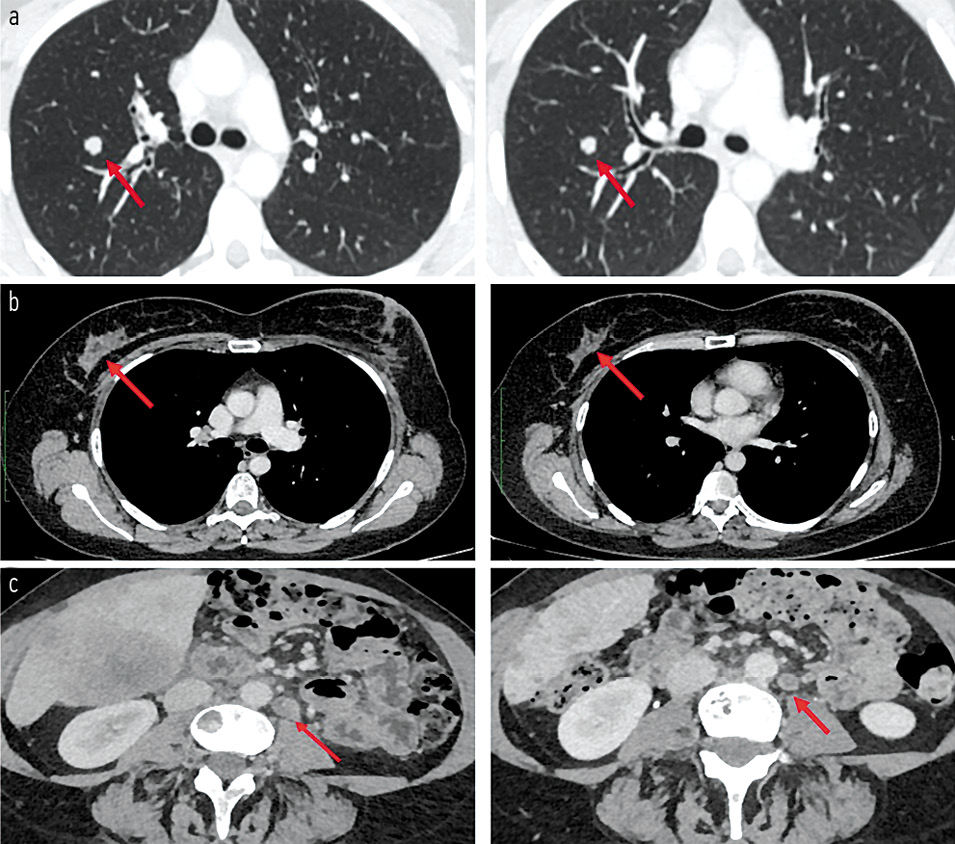

С апреля 2018 г. пациентка начала лечение в запланированном режиме. Первыми эффектами, которые пациентка ощутила субъективно уже через 8 нед, стали уменьшение интенсивности боли в поясничном отделе и снижение частоты приступов кашля. Объективные данные (оценка по КТ согласно критериям RECIST1.1) подтвердили уменьшение суммы наибольшего размера таргетных очагов на 10%, что укладывалось в стабилизацию заболевания. Максимальный эффект лечения достигнут через 24 нед – отмечено выраженное уменьшение размеров первичной опухоли и метастатических очагов, что соответствовало ЧО (-40%; рис. 5). Наиболее крупные очаги в легких уменьшились в рамках стабилизации, а более мелкие исчезли вовсе. Клинически пациентку перестали беспокоить боль в пояснице и приступы кашля (SpO2 – 98%).

Рис. 5. КТ-снимки, выполненные до начала лечения и после 30 циклов. Красными стрелками отмечены опухолевые очаги: a – метастаз в легком, b – первичная опухоль в молочной железе, с – метастатический лимфатический узел. / Fig. 5. CT scans before treatment and after 30 cycles. Red arrows indicate tumor foci: a – metastasis in the lung, b – primary tumor in the breast, c – metastatic lymph node.